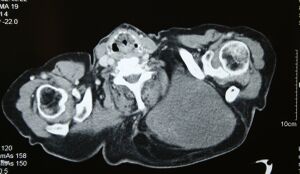

MRI of myxoid liposarcoma of high grade, in left axillary region of 40 year old man. Highlighted by the white color. Horizontal section.